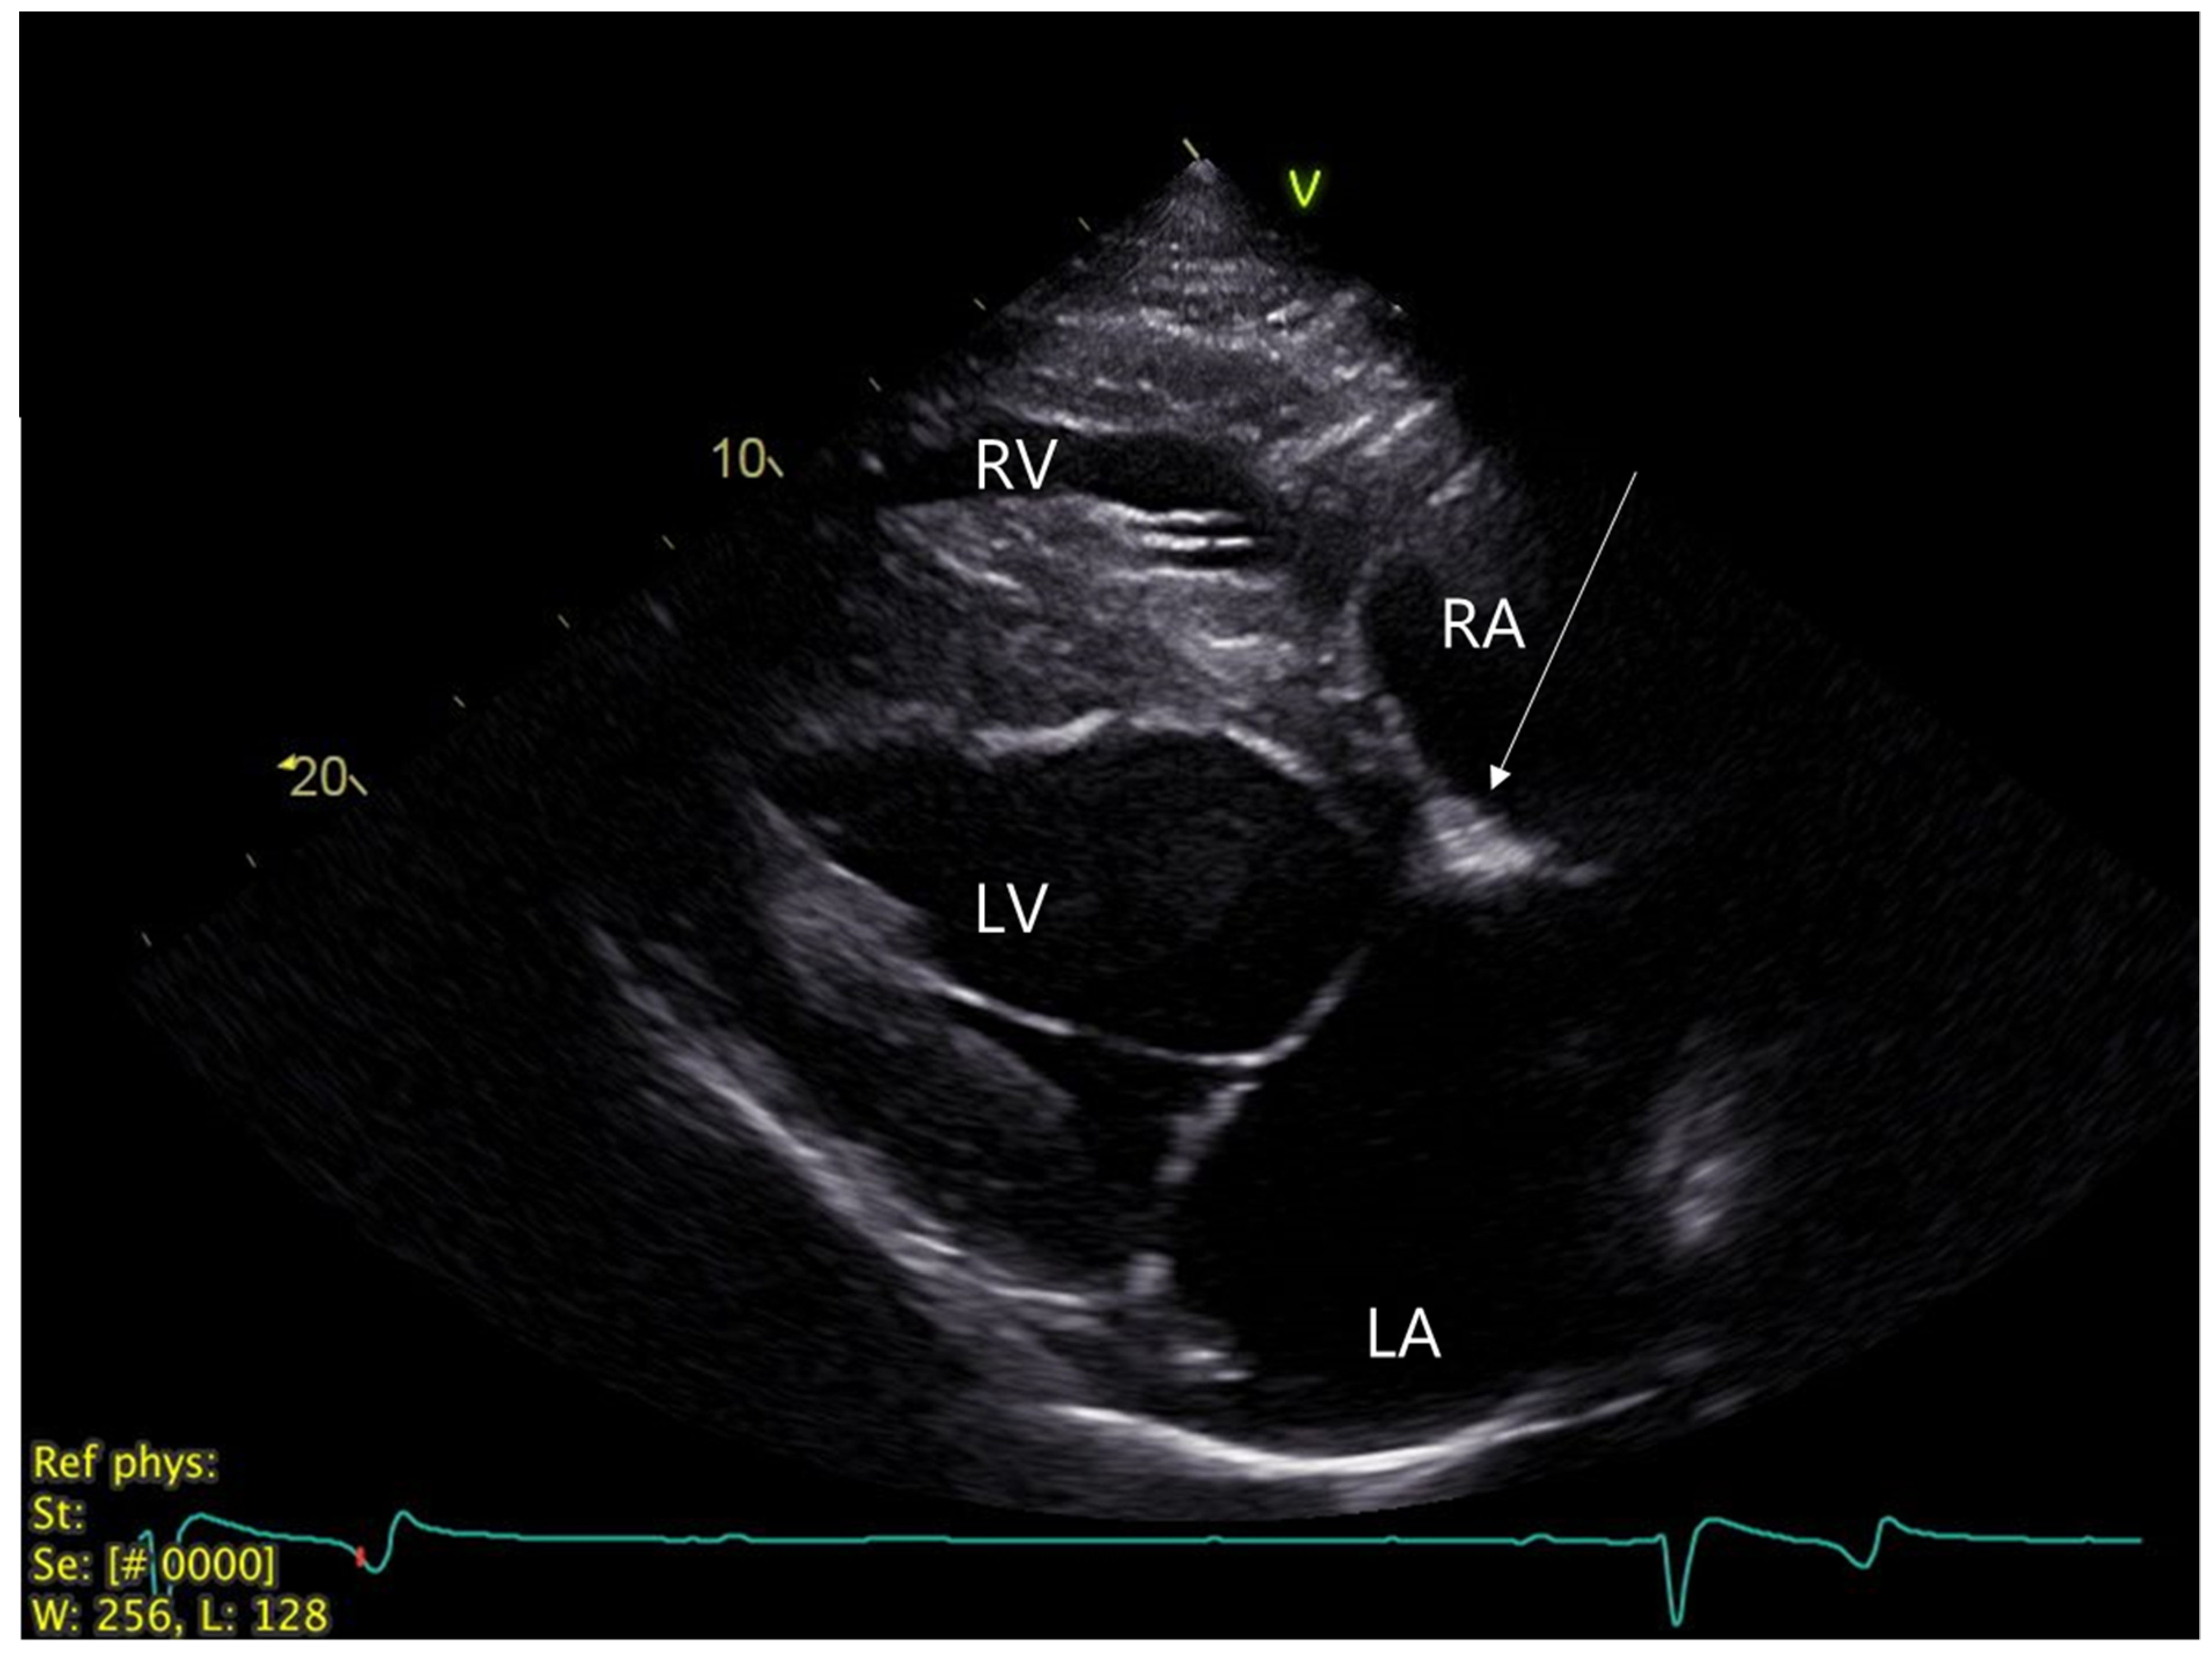

Echocardiography was performed with a portable Vivid IQ ultrasound system (GE Healthcare, Chicago, IL, USA) with a 1.3–4.0 MHz phased array transducer and showed a normal heart size and function. An intermittent trivial (nonaudible) mitral valve regurgitation was visible with color Doppler echocardiography. In the right parasternal, long-axis, four-chamber view of the heart, a slightly hyperechoic area (~1.5 × 0.8 cm) in the AV nodal region was observed (Figure 2). An implantable loop recorder (ILR, Reveal LINQ, Medtronic, Minneapolis, MI, USA) was inserted subcutaneously in the 5th intercostal space, as previously described [13], in order to monitor the cardiac rhythm further upon discharge. The ILR was programmed to detect pauses above 4.5 sec in duration.

Figure 2. Echocardiogram. Right parasternal, long-axis, four-chamber view of the heart with focus on left atrium. Arrow highlights hyperechogenic zone in the proximal interventricular region (AV nodal area). AV: Atrioventricular, LA: Left atrium, LV: Left ventricle, RA: Right atrium, RV: Right ventricle.